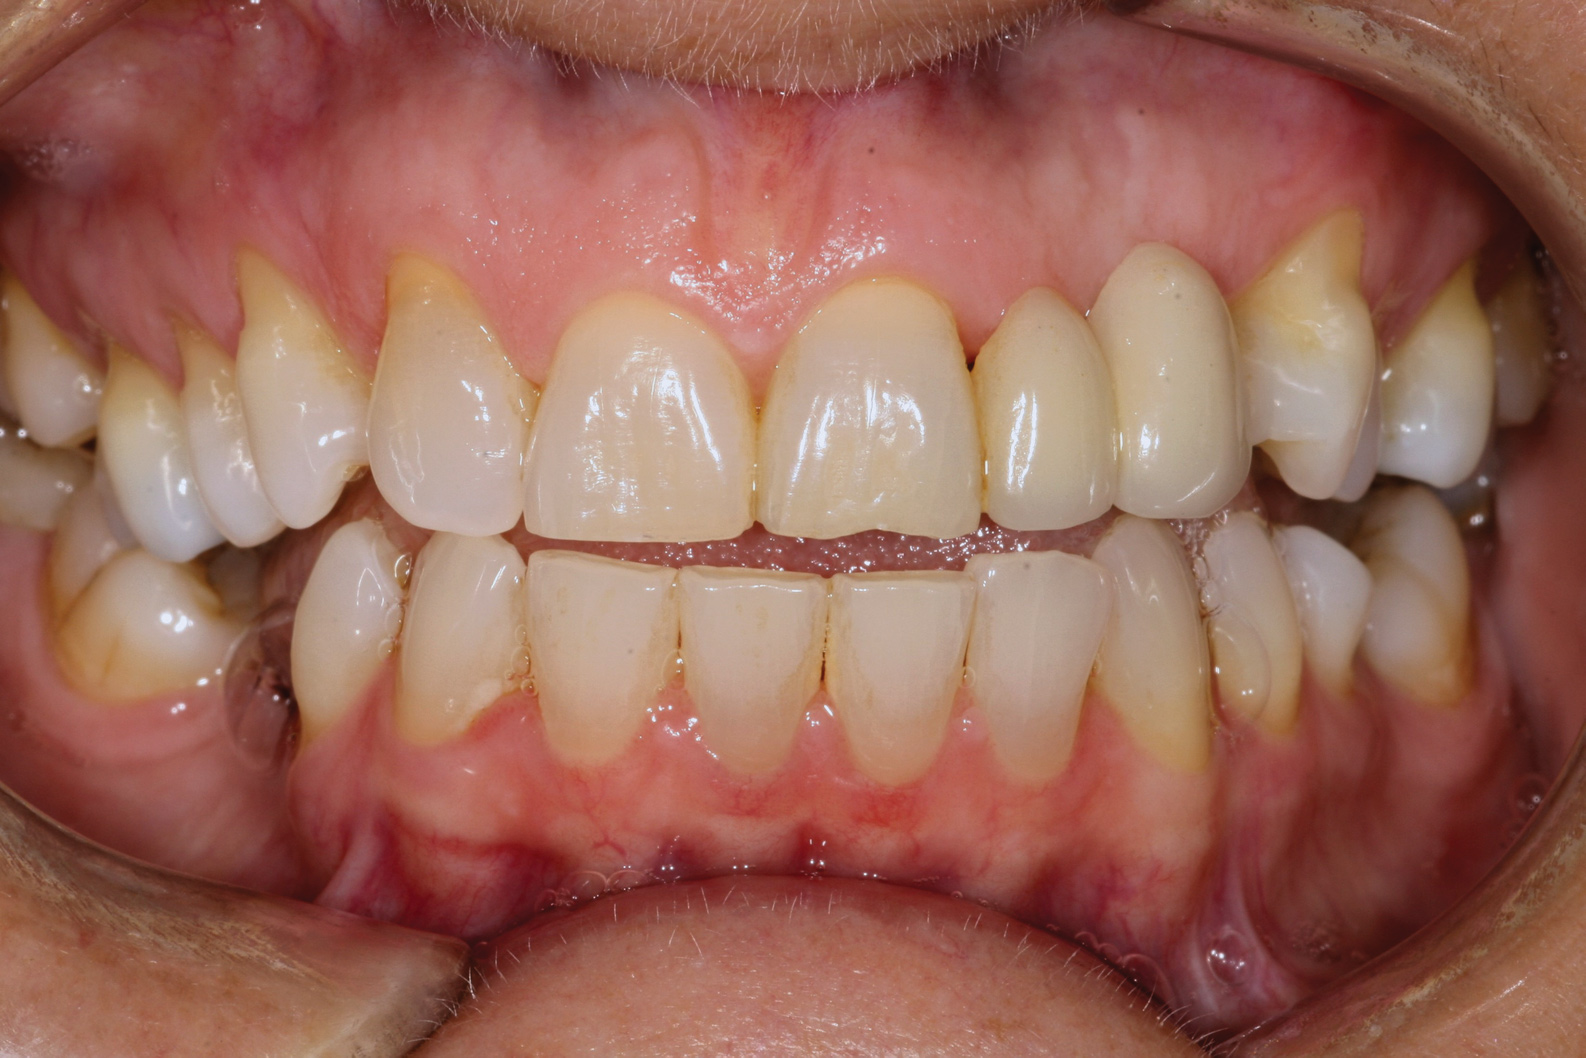

Fig 1. Miller Class I recession on tooth No. 11 (Fig 1) treated with tuberosity CTG (Fig 2). Note this CTG (which is the tuberosity CTG from Fig 5) was placed before the practitioner developed thinning techniques, so a keloid-like appearance was observed even 1 year after grafting.

Figure 1

Fig 2. Miller Class I recession on tooth No. 11 (Fig 1) treated with tuberosity CTG (Fig 2). Note this CTG (which is the tuberosity CTG from Fig 5) was placed before the practitioner developed thinning techniques, so a keloid-like appearance was observed even 1 year after grafting.

Figure 2

A complication in using CT from the tuberosity reported in the literature is a tendency for clinicians to harvest tissue that is too thick.12 This can result in a keloid-like appearance similar to what may occur with an EPG. This excess thickness can be unesthetic (Figure 1 and Figure 2) and subsequently require a gingivoplasty to remove the superfluous tissue.12 This problem may perhaps be alleviated with proper thinning of the graft prior to insertion into the recipient area.